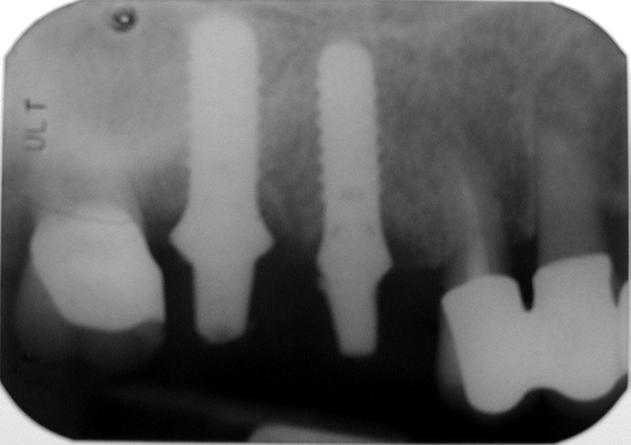

Jedná se o vyzvednutí membrány, která čelistní dutinu vystýlá, pod vyzvednutou membránou vznikne kapsa, kam se umístí augmentační materiál, do kterého se zavedou implantáty.

Vhojení implantátů se při této operaci prodlužuje na 6-12 měsíců.